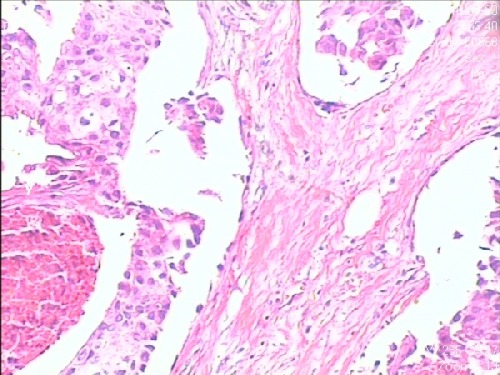

“左”乳浸润性导管癌。